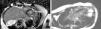

Presentamos el caso de un varón de 13 años de edad, sin antecedentes de interés, que acude a su centro por dolor torácico de carácter punzante, ocasional, sin cortejo vegetativo, ni irradiación, que varía con la respiración y aumenta con el decúbito. Odinofagia sin fiebre en los días previos. Valorado por su pediatra, inició tratamiento con ibuprofeno, cediendo el dolor, que reapareció a las 8 h. En el hospital de origen, se realizó una radiografía de tórax que no mostró afección y un ECG en el que se apreciaba ascenso del ST en la cara inferior y lateral (fig. 1). Aumento de creatincinasa (1.000 U/L) y troponina T (1,5 ng/ml). Trasladado a nuestro centro con sospecha de infarto agudo de miocardio (IAM). A su llegada, el paciente está hemodinámicamente estable, refiriendo dolor ocasional. Se realiza una ecocardiografía, que no muestra alteraciones. Se inició tratamiento antiinflamatorio y anticoagulante con enoxaparina, permaneciendo monitorizado en la Unidad de Cuidados Intensivos, con desaparición del dolor en las horas siguientes. La angio-RM mostró un patrón de realce tardío con gadolinio en la cara inferior a todos los niveles y en la cara lateral a nivel medio y apical>50%, compatible con miocarditis (fig. 2). El ECG a las 12h muestra normalización del segmento ST, persistiendo inversión de la onda T en la cara inferior (fig. 1). Se apreció normalización enzimática a las 72 h. El resto de los estudios complementarios (cultivos, serologías víricas, autoanticuerpos, perfil lipídico y estudio de coagulopatías) fueron normales. Alta a los 6 días completamente asintomático, con ECG, ecocardiografía y enzimas dentro de la normalidad.